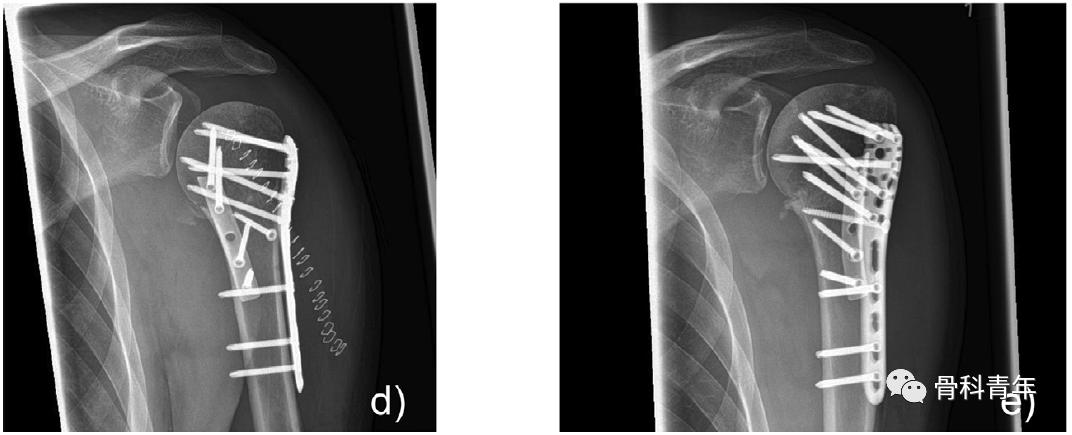

典型病例:a/b,术前X线及CT;e/f,术后4月复查。

手术切口采用经三角肌胸大肌入路,在肱骨近端复位,纠正内翻后,先放置肱骨外侧PHILOS钢板,如患者存在骨量降低,可注入骨水泥加强,后在肱骨小结节处置入1/3管型钢板。管型钢板的位置,近端应置于大结节,肩胛下肌止点处,钢板跨过结节间沟,钢板远端置于胸大肌肌腱止点的外侧。

骨折复位后,先外侧置入PHILOS钢板

管型钢板塑形后,置于小结节